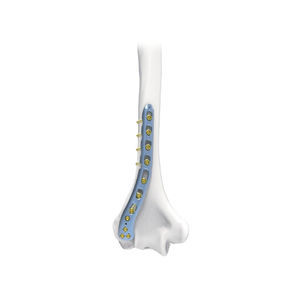

... 肱骨远端后侧锁定接骨板左 8 孔 肱骨远端后侧锁定接骨板 10 孔左侧 肱骨远端后侧锁定接骨板 12 孔左侧 肱骨远端后侧锁定接骨板 14 孔左侧 肱骨远端后侧锁定接骨板 右 8 孔 肱骨远端后侧锁定接骨板 10 孔右 肱骨远端后侧锁定板 12 孔 右 肱骨远端后侧锁定板 14 孔 右 ...

... 肱骨远端背外侧锁定钢板 肱骨远端骨折、骨不连、截骨和假关节的固定(背外侧入路),尤其适用于骨质疏松的成年患者。 ...

... TRUE LOCK 肱骨远端后外侧接骨板适用于。 - 肱骨远端关节内骨折。 肱骨远端关节内骨折。 - 肱骨远端髁上骨折。 - 肱骨远端非关节炎。 - 肱骨远端截骨术。 肱骨远端骨折占所有骨折的2%,约占肱骨骨折的1/3。 骨折的三分之一。 解剖板;右侧和左侧。 在3-9之间有4个孔可供选择。 TRUE LOCK 肱骨远端后外侧接骨板是由Ti6Al4V ELI材料(ASTM F136)制成。 ...

Truemed Medical